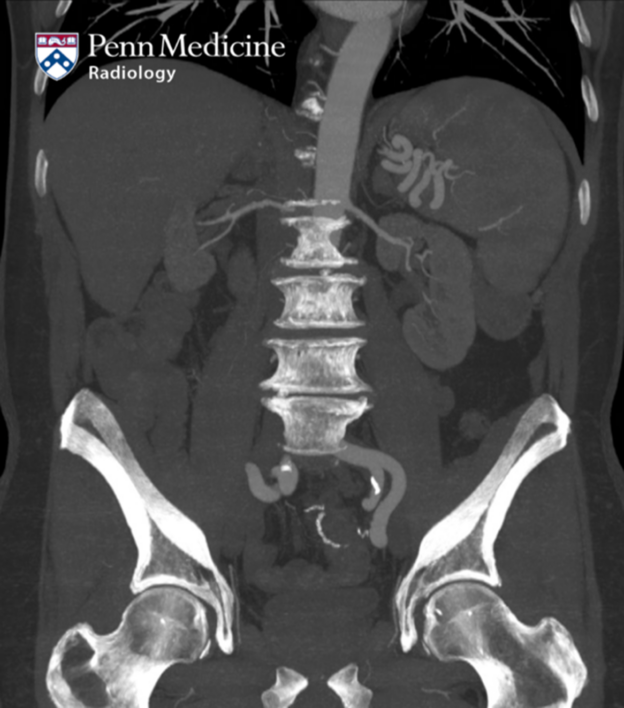

68-year-old man with chronic mesenteric ischemia and abdominal fullness

A 68-year-old man with a history of chronic mesenteric ischemia presented with abdominal fullness.